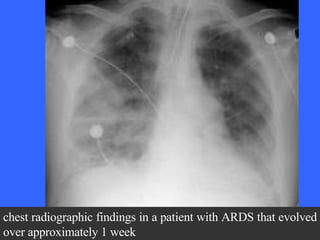

Chest radiograph shows an endotracheal tube, left subclavian central venous catheter into the superior vena cava, and bilateral patchy opacities in mostly the middle and lower lung zones.  The patient had been in respiratory failure for 1 week with the diagnosis of ARDS.

chest radiographic findings in a patient with ARDS that evolved over approximately 1 week

Chest radiograph showsan endotracheal tube, left subclavian central venous catheter into the superior vena cava, and bilateral patchy opacities in mostly the middle and lower lung zones. The patient had been in respiratory failure for 1 week with the diagnosis of ARDS.

chest radiographic findingsin a patient with ARDS that evolved over approximately 1 week